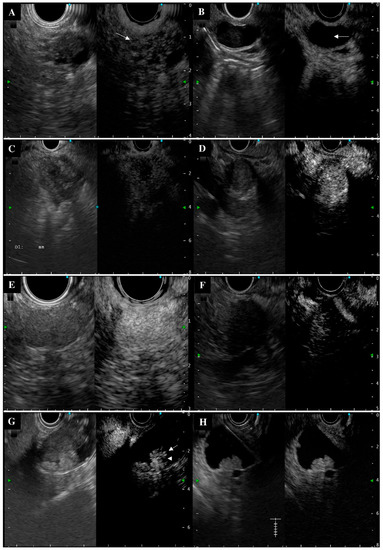

3.3. Typical and Atypical Contrast-Enhanced Harmonic Endoscopic Ultrasonography Imaging

| Final Diagnosis | Typical Contrast | Atypical Contrast |

|---|---|---|

| IPMA with mucinous clot | 110 (85.3) A | 19 (14.7) |

| IPMC with mural nodule | 28 (87.5) B | 4 (12.5) |

| Pancreatic cancer | 23 (67.7) C | 11 (32.4) |

| Pancreatic neuroendocrine neoplasm | 12 (75.0) D | 4 (25.0) |

| Gallbladder carcinoma | 22 (68.8) E | 10 (31.3) |